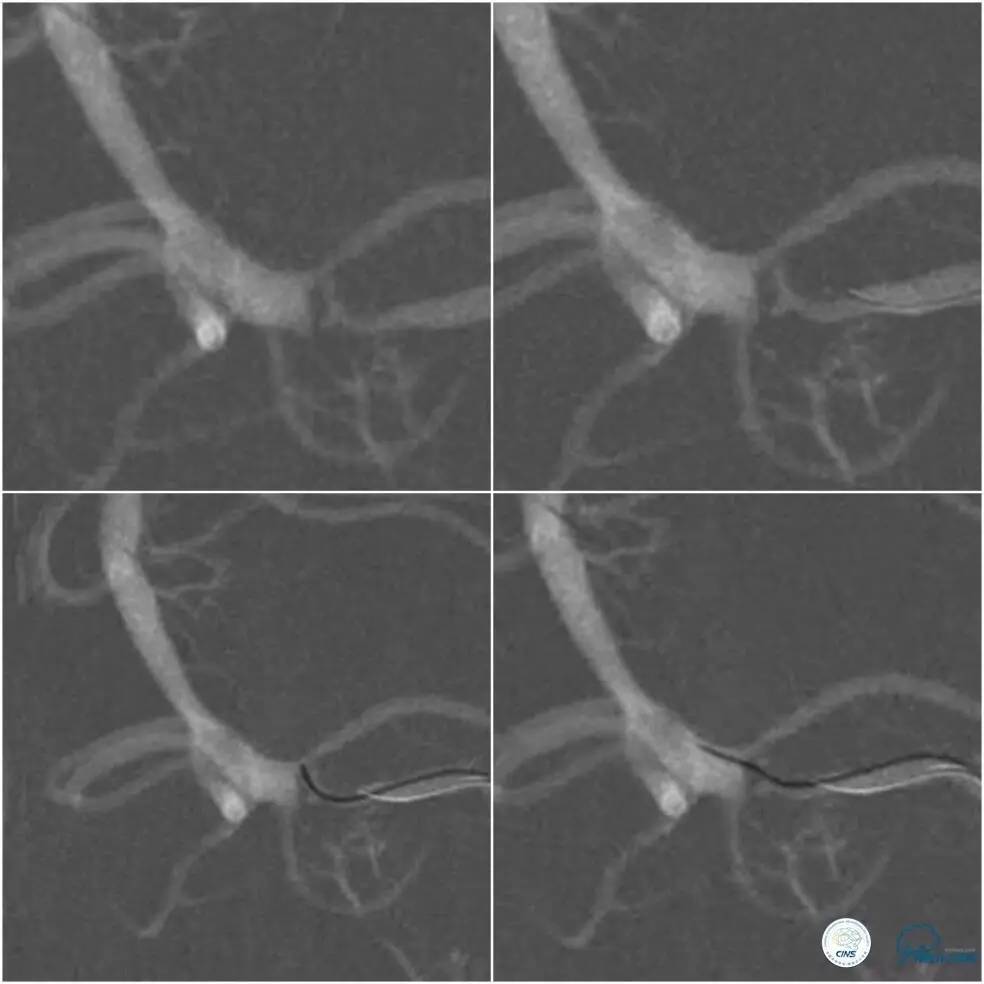

治疗中最大困难如术前估计是微导丝过病变困难,原因是病变狭窄程度重,且成角(斑块偏心因素加重病变成角)。在将微导丝(Traxcess,0.014")头端塑了一个小弯后,微导丝艰难通过病变(图8)。

图8

微导丝到位后,原想跟进微导管(Echelon 10)行微导管造影证实在真腔,但因微导管无法越过病变而作罢。将微导丝后接Dockling延长导丝后撤出微管,依次送入Gateway1.5 mm x 9 mm,2.0 mm x 9 mm球囊预扩后,放置Winspan 3.5 mm x 15 mm支架(图9)。术后前向血流明显改善,残余狭窄约15%(图9)。

图9